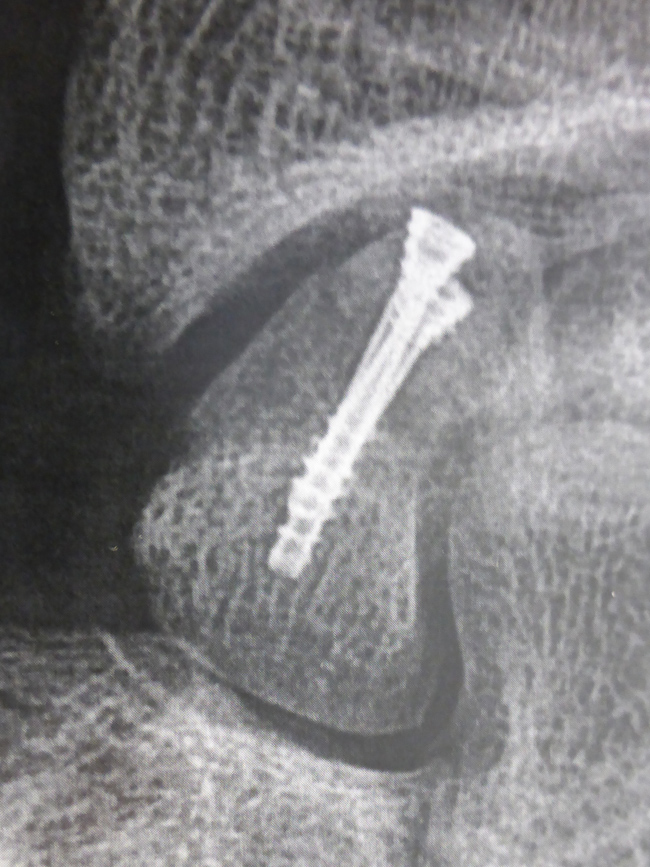

C’est la technique traditionnelle. C’est celle qui entraîne le moins de risque de complications. L’immobilisation doit être conservée en permanence jusqu’à consolidation ce qui nécessite un arrêt de travail prolongé. - soit par vissage à foyer fermé c’est à mise en place d’une vis à l’intérieur du scaphoïde, au bloc opératoire sous contrôle radiologique.

L’intervention est réalisée sous anesthésie locale, en ambulatoire.

La vis est introduite à travers la peau par une très petite incision .

La vis est introduite par une toute petite incision. La position de la vis est contrôlée par des radiographies pendant l’intervention.

Une fois réduite, la fracture est toujours stabilisée par une vis ou des broches mise en place au bloc opératoire.

Ces fractures sont particulières car le pôle proximal du scaphoïde est la partie du scaphoïde qui consolide le plus difficilement. Il est maintenant admis que ces fractures doivent toujours être fixées chirurgicalement, même si elles ne sont pas déplacées. On utilise habituellement une ou deux vis.